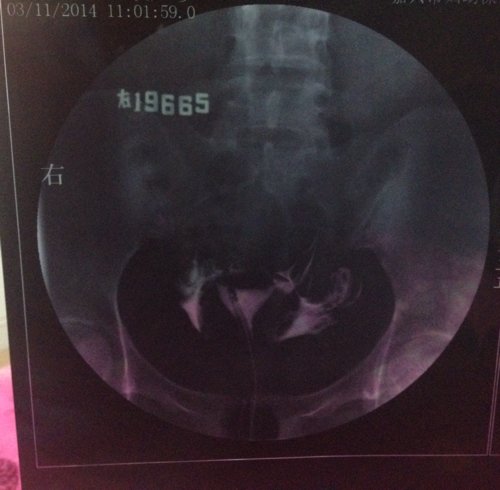

上个月输卵管造影的结果,这个月想试孕又发现卵泡没排出来,现在纠结要不要打促排卵针,片子上看起来严重 上个月输卵管造影的结果,这个月想试孕又发现卵泡没排出来,现在纠结要不要打促排卵针,片子上看起来严重吗?这个月是右卵巢有优势卵泡。医生帮忙看下,我这情况能打促排卵针吗? 点击展开 匿名用户 2014-05-11 00:08 为您推荐: 其他回答 病情分析: 你好,应该予以手术治疗的 指导意见: 可以考虑腹腔镜手术来治疗,术后注意不可过早恢复同房,及时复查。 独水凡_xjeq 2014-05-11 10:34 相关问题 3月做的输卵管造影,两侧通而欠畅,4月做卵泡监测,发现卵泡大了不排,5月刚打了促排卵针,请问我宫外 之前做造影,结果是左侧通,右侧不通,后来做输卵管通液通了,现在右侧卵泡2 1请 请问:(南京鼓楼医院)做(生殖激素测定+基础卵泡检查)跟(子宫输卵管浀造影)跟(甲功三项)大概